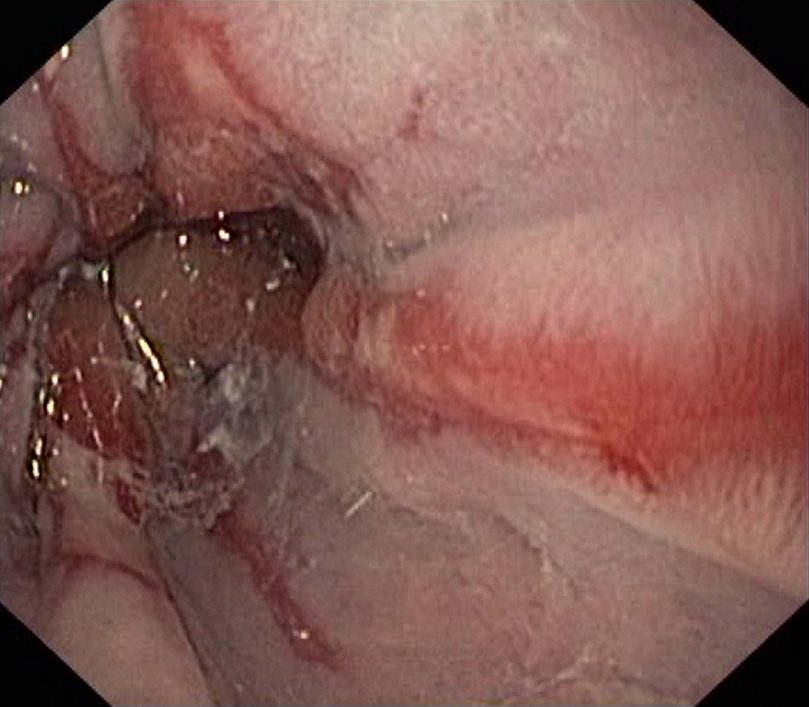

Reflux Oesophagitis Grade D (LA Classification). Just click on a picture!

Reflux Oesophagitis Grade D (LA Classification)